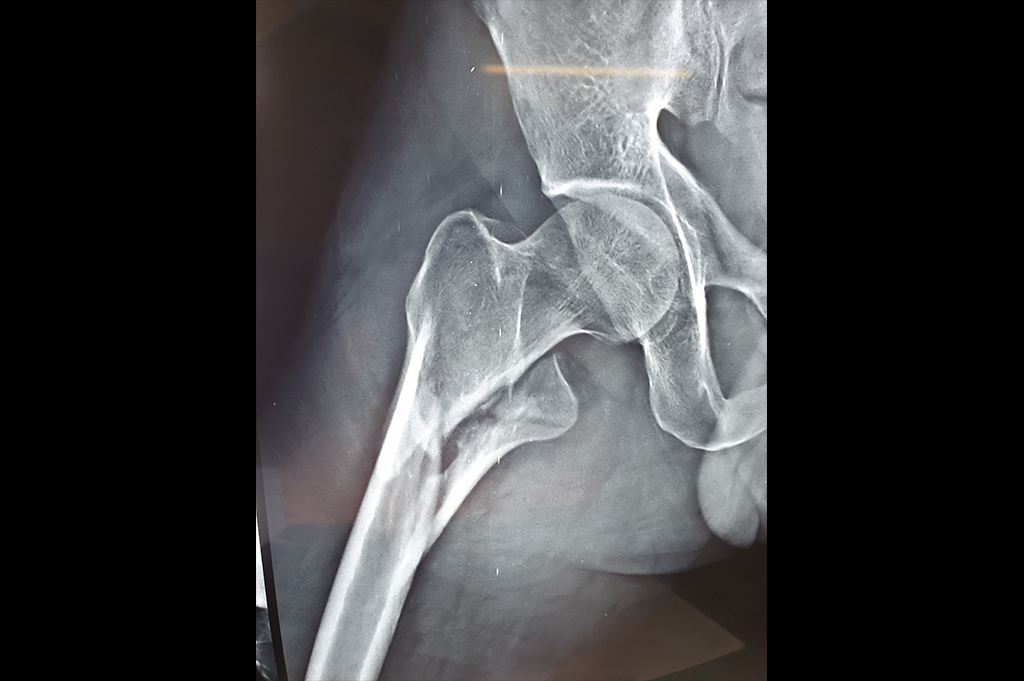

Neck Femur Fracture